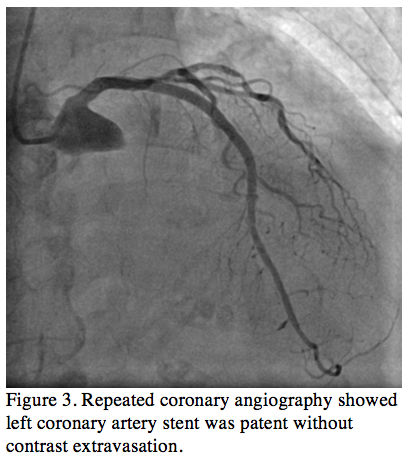

Figure 4. Echocardiogram showed small pericardial effusion with posterior-lateral localization (arrow) (click thumbnail to view larger image).

Repeat echocardiogram demonstrated a small pericardial effusion localized to the posterior-lateral compartment (Figure 4). Non-steroidal anti-inflammatory drugs (NSAIDs) were started because of suspected acute pericarditis and chest pain improved significantly by the second day of treatment. Blood cultures were sterile and serum cardiac biomarkers remained within normal limits during the follow-up. On the fifth day after the procedure, the ECG showed virtual complete resolution of the ST-segment elevation without pathologic Q-wave (Figure 1C). The patient was discharged 6 days later with routine follow-up scheduled.